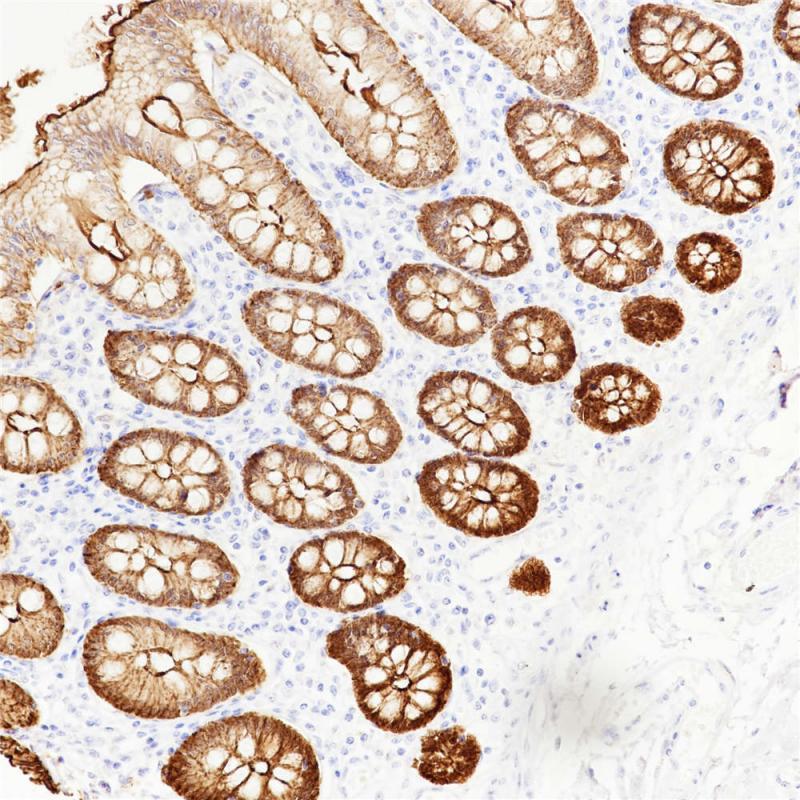

Villin是一种分子量约为93kDa的钙调肌动蛋白,主要与调节肌纤维聚集活动相关。它是肠道和肾小管上皮细胞的刷状缘微绒毛的主要组成成分。在正常组织中,Villin只在胃肠道以及泌尿道的上皮中表达。在肿瘤组织中,Villin在大肠癌、肝细胞癌、子宫内膜癌、卵巢癌和肺癌中均有表达。Villin通常被用于鉴别直肠转移癌与其他胃肠道原发癌。

阳性对照

结肠